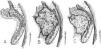

MétodosRealizamos un análisis retrospectivo de 19 casos de tumores neurogénicos de la región sacra diagnosticados y operados en nuestro centro, de los cuales ocho eran hombres y 11 mujeres, registrando una edad media al diagnóstico de 51 años (con un rango de edades entre 25 y 78 años). Seis se encontraban asintomáticos y fueron diagnosticados incidentalmente, mientras que la mayoría (11 pacientes) presentaban dolor lumbar acompañado de otros síntomas: dolor irradiado a miembros inferiores (MMII), dolor pélvico, alteraciones sensitivas y pérdida de fuerza en MMII. Dos pacientes presentaban otro síntoma principal al diagnóstico: dolor pélvico y en miembro inferior izquierdo (MII). A todos los pacientes se les realizó como mínimo una prueba de imagen (RM/TC). Nueve pacientes tenían tumores limitados al sacro o con extensión posterior, practicándose una intervención por vía posterior. En seis se realizó un abordaje exclusivamente por vía anterior debido a la localización presacra de la tumoración; y en cuatro de ellos fue preciso un abordaje tanto anterior como posterior.

ConclusionesSe debe considerar el gran tamaño que pueden alcanzar estos tumores, su relación con estructuras y la extensión anterior o posterior para seleccionar el abordaje. Resecar la mayor cantidad posible de masa tumoral aporta un mayor beneficio al paciente; al disminuir las posibilidades de recidiva tumoral sin aumentar las complicaciones intra y postoperatorias cuando se utilizan además equipos multidisciplinares.

MethodsWe conducted a retrospective analysis of 19 cases of patients with neurogenic tumors in the sacral area who were diagnosed and underwent surgery at our center. Of them, 8 were male and 11 were female. They had a mean age at diagnosis of 51 years (with an age range of 25-78 years). Six patients were asymptomatic and were diagnosed incidentally, while the majority (11 patients) presented with lumbar pain accompanied by other symptoms: pain radiating to the legs, pelvic pain, sensory alterations and loss of strength in the legs. Two patients presented with another primary symptom on diagnosis: pain in the pelvic region and in the left leg. All patients underwent a least one imaging test (MRI/CT scan). Nine patients had tumors limited to the sacrum or with subsequent spread, with surgery via the posterior route. In 6 cases, an exclusively anterior approach was employed owing to the pre-sacral location of the tumor; 4 cases required both an anterior and posterior approach.

ConclusionsWhen selecting the approach, the large size that these tumors can reach, their relationship with structures, and their anterior or posterior spread should be taken in to account. Resecting the tumor mass as much as possible provides greater benefit to the patient, as this decreases the odds of tumor recurrence without increasing intraoperative and postoperative complications when multidisciplinary teams are also used.